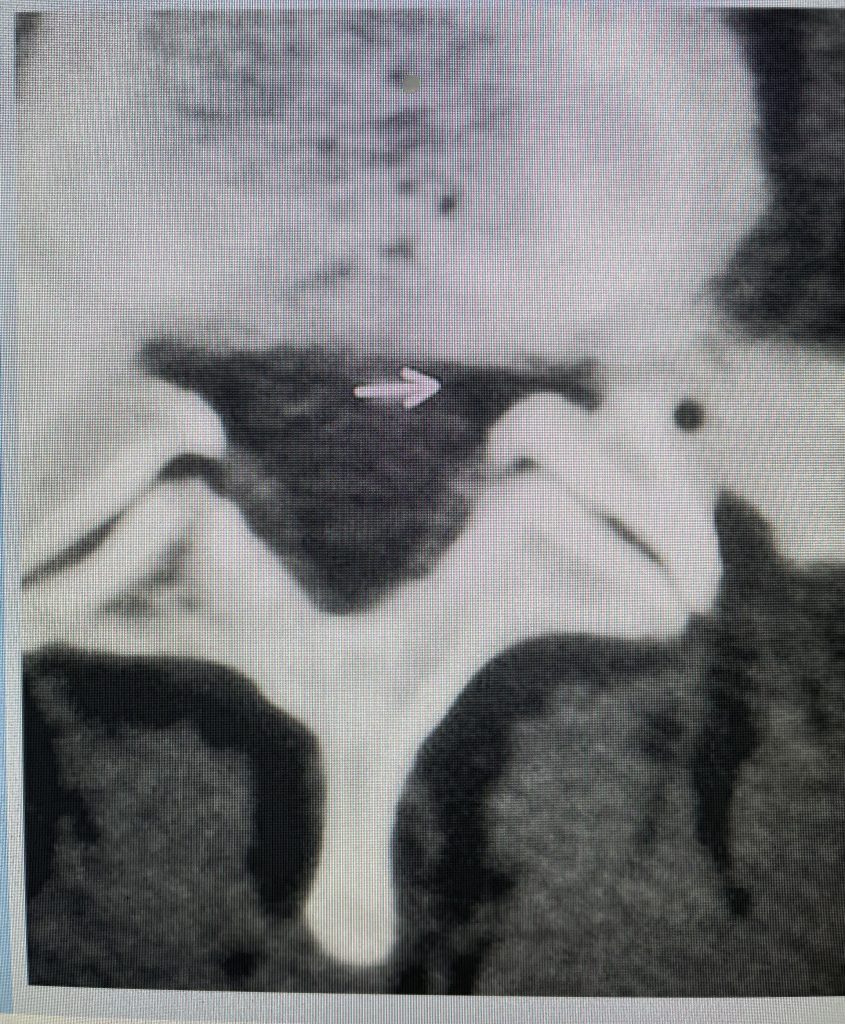

Lateral recess stenosis typically involves compression of the nerve root as it takes off from the thecal sac, prior to entering the nerve foramen or tunnel. In lateral recess stenosis there is narrowing of less than 5 mm between the facet superior articulating process and the posterior vertebral margin and is bounded laterally by the pedicle. The nerve root gets caught medial to the pedicle. The nerve is compressed commonly from thickened ligamentum, short pedicles, or in particular an enlarged superior facet process which compresses the nerve as it descends prior to going underneath the pedicle in a region that is designated as the subarticular recess. (Figs 1, 2, and 3) With lateral recess stenosis, for example, of the L4-5 subarticular recess, the descending L5 nerve root will be compressed by the corresponding L5 superior facet. With foraminal stenosis the actual nerve root is compressed beyond the medial pedicular zone which can be caused by a far lateral type disc facet hypertrophy, tumor, or subluxation.

Figure 2: Cartoon axial image of the lumbar spine showing (arrow) severe narrowing of the lateral recess with flattening of the nerve root compared to a normal nerve root on the opposite side.